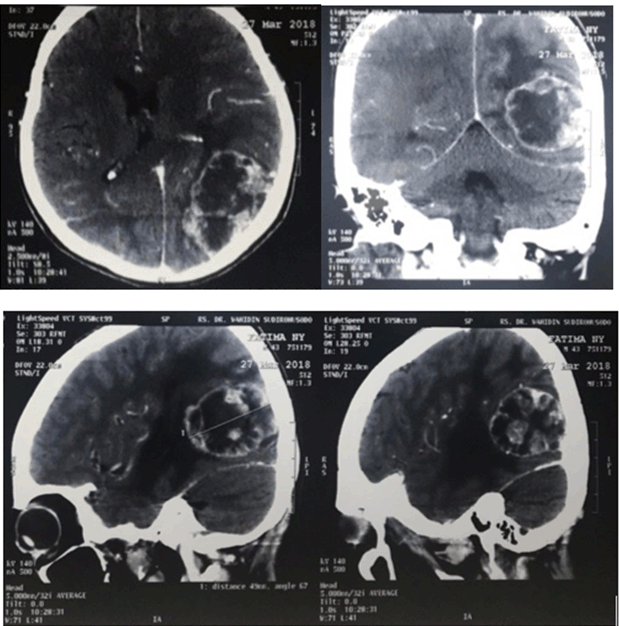

A 41-year-old woman with cervix carcinoma was referred from Gynaecology department with sudden decrease of vision and family noticed she had a squint from last three days. She complained a severe headache and vomiting. There was history of chemotherapy for two cycles and was discontinued about two years ago. Visual acuities were hand movement on both eyes, there was limitation of abduction on right eye (Figure 3). Anterior segments was normal. Funduscopy showed papilledema on both eyes (Figure 4). Head Multiple Slice Computed Tomography (MSCT) scan with contrast on axial slice showed heterogenous lesion and enhanced with contrast with irregular solid, firm edges, sized 4.2x5.8x4 cm, with focal edema around which pushed and narrowed the left lateral ventricle, which caused midline shift 0.5 cm to the right in parietooccipital lobe sinistra suggesting anaplastic astrocytoma (Figure 5).

Figure 5: Multiple slice computed tomography scan with contrast showed parietooccipital lobes mass, suggestive of anaplastic astrocystoma (arrow).

In this case we found that first patients with breast carcinoma had better visual acuity compared to the second patient. This can occur due to the size of the intracranial lesions. Neuroimaging results support this finding, smaller lesion and superficial location for intracranial mass in the first patient may have not increasethe intracranial pressure while in the second patient with cervix carcinoma, the intracranial lesion is larger with a focal edema and constrict the ventricle results a midline shift. All of which would increase the intracranial pressure thus papilledema occurs.